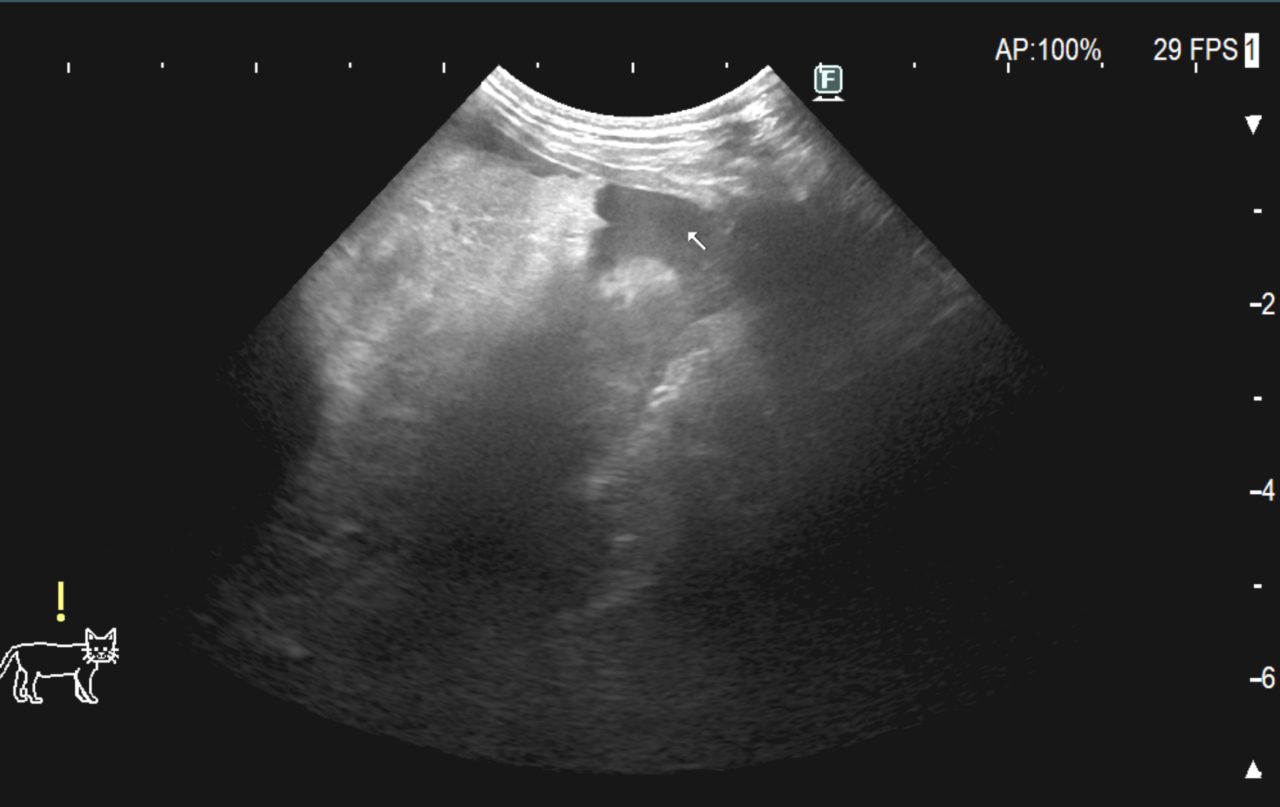

胆嚢粘液嚢腫による胆汁性腹膜炎

13歳のワンコが激しく嘔吐している。尿が濃い黄色になってきた。食欲もなくぐったりしているとのことでかかりつけ医を受診されました。”緊急手術が必要になるだろう”とのことで当センターに紹介受診されました。各種検査の後、胆嚢破裂による胆汁性腹膜炎と診断し、開腹下で胆嚢摘出術、腹腔洗浄を実施しました。胆嚢は沈黙の臓器と言われているので、定期的に胆嚢を超音波で評価しておきましょう。粘液嚢腫が見つかれば破裂する前に摘出することをおすすめします。予防に勝る治療はありません。